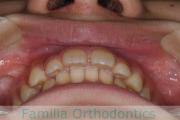

No.22V-244

- 主な症状:

- 上顎前突

- その他の症状:

- 叢生

- 年齢:

- 14歳

- 性別:

- 女性

- 抜歯部位

- 上:

- 44

- 下:

- 8558

- 主な使用装置:

- FEA

- 治療にかかった費用:

- 88万円

上の前歯を治したいとのことで来院されました。かなり強い前歯の突出がありましたので、上下左右から小臼歯を抜歯して、マルチブラケット法を行いました。約2年半、30回程度の通院が必要でした。前歯の移動量が多い上顎前突(出っ歯)の治療は、前歯の歯根吸収のリスクが特に高めです。